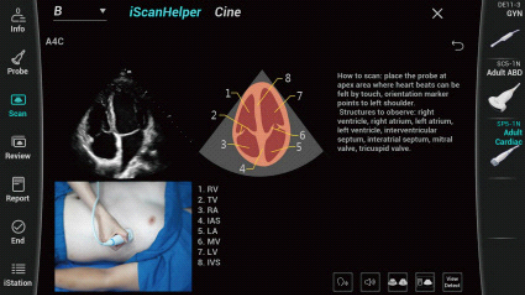

Dise?ado especĂficamente para usuarios de atenciĂłn primaria, el equipo Consona presenta soluciones nuevas y concretas que lo ayudan a realizar diagnĂłsticos sin problemas y de manera eficiente en diversos tipos de pacientes.

Independientemente de si lleva a cabo su rutina en hospitales o clĂnicas, o si estĂĄ perfeccionando sus habilidades en aplicaciones de diagnĂłstico por imĂĄgenes generales, atenciĂłn de la salud de la mujer o especialidades cardiovasculares, esta serie dispone de herramientas muy potentes para que se mantenga a la vanguardia.